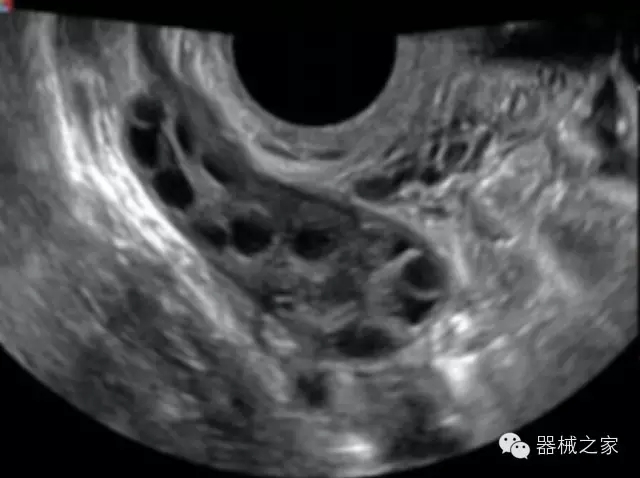

臨床圖片賞析

產(chǎn)品特點

·全球目前唯一一款配備主機(jī)雙探頭接口,整機(jī)重量(含電池)在5公斤以內(nèi)的便攜式彩超;

·一款互聯(lián)網(wǎng)彩超,只要有手機(jī)信號的地方就可以非常方便地實現(xiàn)遠(yuǎn)程會診和病案調(diào)?。?/span>

·鎂鋁合金外殼,堅固可靠耐用;

·獨有的HoloTM PW 實時3取樣門PW成像技術(shù),精確進(jìn)行血管診斷;

·一鍵優(yōu)化B、Color、PW,Auto Doppler自動識別血管位置、偏轉(zhuǎn)角度等,提高工作效率;

·30°超廣角精細(xì)偏轉(zhuǎn)成像技術(shù),更優(yōu)異的頻譜圖像;

·W+智能搜索引擎,快速尋找圖像;

·SSD、USB3.0保障開機(jī)快,導(dǎo)出圖像更快,減少等待時間;

·WIFI、網(wǎng)口、3G,多重聯(lián)網(wǎng)方式,全天候保障云端備份,不再擔(dān)心圖像丟失;